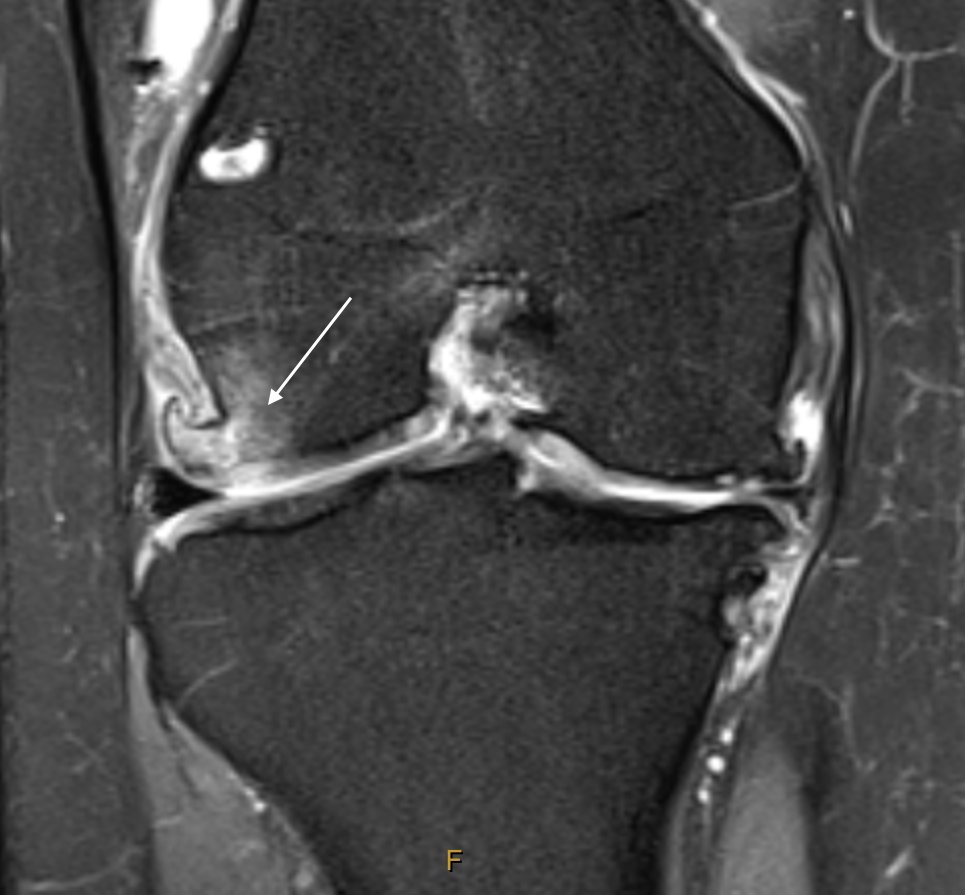

Consent ✅ Late 20s, cyclist / runner ACL reconstruction, then re-rupture managed conservatively Now quite marked OA knee - pain always medial until heavy fall off bike & awkward valgus injury Now lateral pain MRI - fractured, oedematous lateral femoral condyle osteophyte -